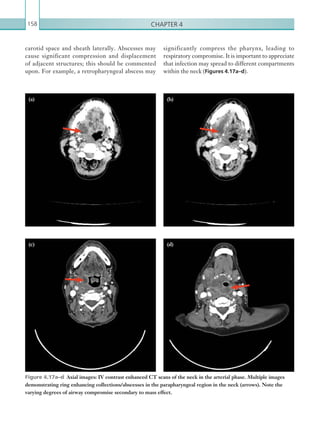

Gastrointestinal and genitourinaryimaging 47 Computed tomography Appearances on CT are similar to those seen on plain film images. SBO is present with dilated fluid-filled small bowel loops measuring 3.5 cm. As with any case of obstruction, the entire length of bowel must be traced. A transition point (abrupt calibre change between dilated and non-dilated bowel) may be identified and is the likely site of the impacted gallstone (Figure 2.32). Care should be taken, as not all gallstones are calcified (12%) and they may be of similar density to the bowel contents (Lassandro et al., 2005). Multiple stones may also be present. Pneumobilia on CT is identified as branching air- filled structures in the liver (Figure 2.33). These can be differentiated from similar appearances of portal venous gas, as air in the biliary tree does not extend to the periphery of the liver, unlike portal venous gas. Causes of pneumobilia are listed in Table 2.11. Figure 2.33  Axial image: IV contrast enhanced CT scan of the abdomen in the portal venous phase. Gas is seen within the biliary tree (arrow). There is a small volume of fluid around the liver. • Recent endoscopic retrograde cholangiopancreatography or percutaneous transhepatic cholangiography. • Gallstone ileus. • Biliary enteric anastomosis (e.g. Whipple’s). • Peptic ulcer disease. • Traumatic. • Emphysematous cholecystitis. • Incompetent sphincter of Oddi (sphicterotomy, chronic pancreatitis and passage of stone). • Congenital. Table 2.11  Causes of ­pneumobilia. Figure 2.32  Axial image: IV contrast enhanced CT scan of the abdomen and pelvis in the portal venous phase. A rounded, hyperdense gallstone is seen within the lumen of a small bowel loop in the right iliac fossa. Loops of fluid-filled, dilated small bowel can also be seen. K22247_C002.indd 47 16/05/15 3:07 AM

• 70.

Chapter 248 • Afistulous tract may be seen between the gallbladder and the duodenum and this may be associated with surrounding inflammation and locules of free gas. • It is important to distinguish between portal venous gas and biliary air, which appear similar on CT, the latter not extending to the periphery of the liver. Report checklist • Degree of bowel obstruction/dilatation associated with gallstone ileus. • Presence or absence of associated collections in the gallbladder bed. • Presence or absence of overt free intraperitoneal gas. References Lassandro F, Romano S, Ragozzino A et al. (2005) Role of helical CT in diagnosis of gallstone ileus and relatedconditions. Am J Roentgenol 185:1159–1165. Yu CY, Lin CC, Shyu RY et al. (2005) Value of CT in the diagnosis and management of gallstone ileus. World J Gastroenterol 11:2142–2147. Inflammatory changes may be seen around the gallbladder and second part of the duodenum, with thickening of the gallbladder wall, pericholecystic fluid and surrounding inflammatory fat stranding. There mayalsobeloculesoffreegasandevidenceofthefistula between the gallbladder and duodenum. Occasionally, the inflamed gallbladder can adhere to ascending colon and the gallstone can pass into the large bowel. This may then lead to passage of the stone or it can become obstructed, depending on the size of the stone (Figures 2.34, 2.35). If gallstone ileus is present, the surgical team should be informed; treatment options are usually surgically based, although some patients are managed conservatively. Key points • An AXR showing Rigler’s triad is diagnostic for gallstone ileus. • CT features are similar to those seen on plain film images. The entire bowel should be carefully inspected to identify the transition point or gallstone(s). Figure 2.34  Axial image: unenhanced CT scan of the abdomen. There is thickening of the gallbladder wall, consistent with acute cholecystitis. Figure 2.35  Axial image: unenhanced CT scan of the abdomen. There is an impacted gallstone in the sigmoid colon. K22247_C002.indd 48 16/05/15 3:07 AM

• 71.